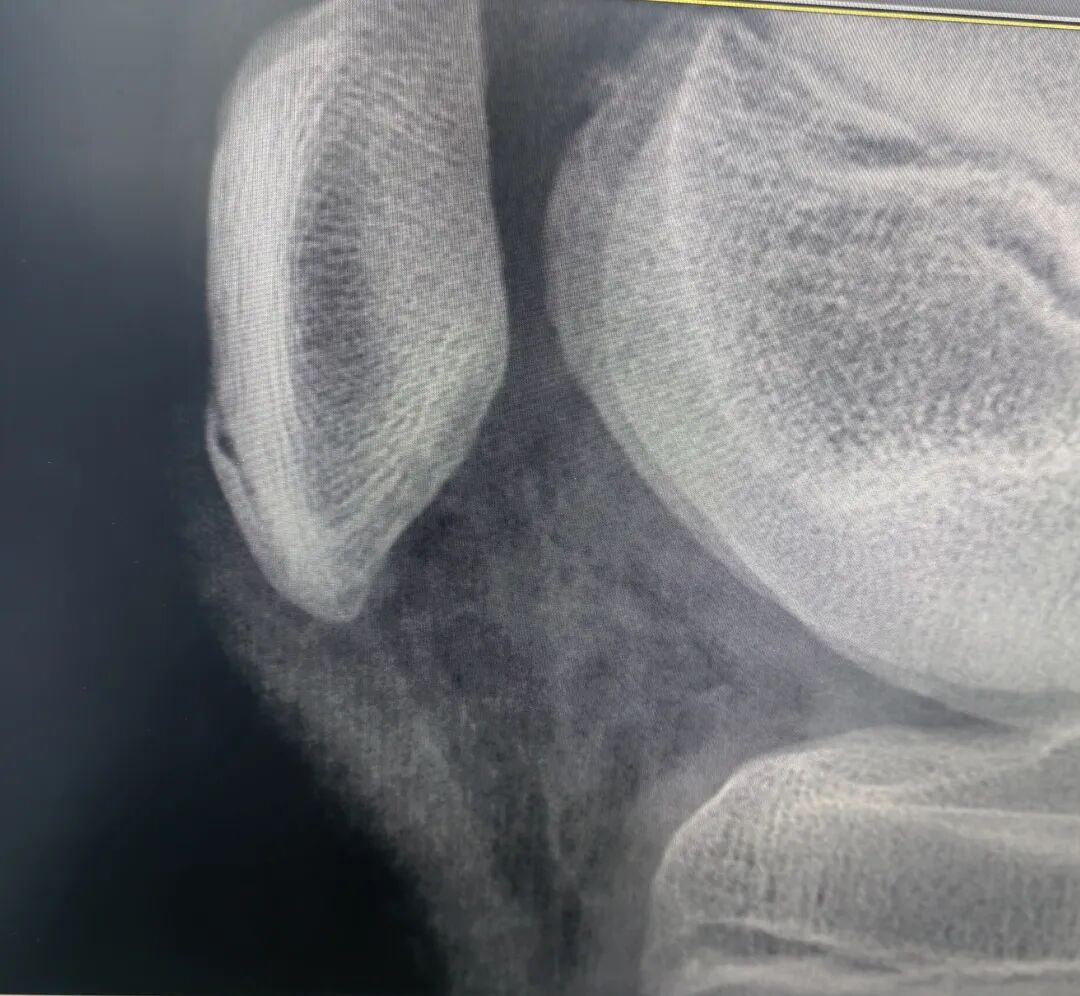

图2 髌骨袖套状撕脱骨折,有两大块骨片从骨性的髌骨下极撕脱。注意髌下脂肪垫(霍法脂肪垫)处伴发的软组织肿胀以及髌腱的增厚情况。